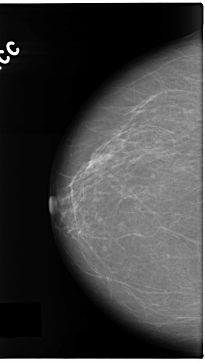

C_0138_1.RIGHT_CC

RIGHT_CC LINES 4712 PIXELS_PER_LINE 2656 BITS_PER_PIXEL 12 RESOLUTION 50 NON_OVERLAY